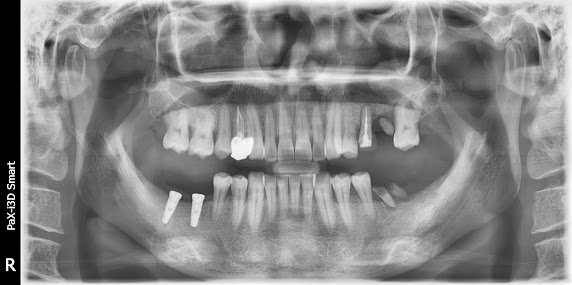

This is a patient photo sent by Dr. Ahn. It's a preoperative picture GBR (Guided Bone Regeneration) was performed using SmartBuilder This is a radiographic image Preoperative and postoperative CT findings Approximately 6 months later, the implant was placed. This is a radiographic image. It still looks a bit unstable.